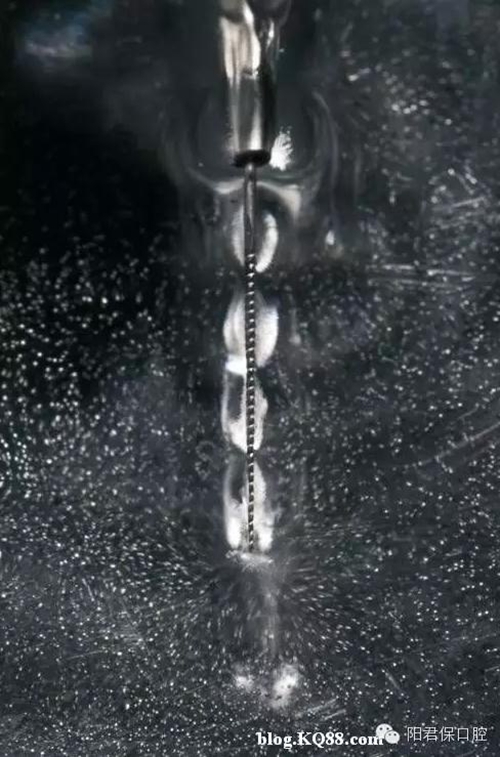

十一,超聲蕩洗

超聲蕩洗能增強清洗效果,超聲銼的持續(xù)震動可以將次氯酸鈉傳送到根尖部,也可以加熱根管內(nèi)的次氯酸鈉,超聲震動的頻率是25-40kHz,超聲在根管內(nèi)形成超聲流,同時在銼尖端形成渦流。超聲流有殺滅細菌和破壞酶的作用,超聲不能用于根管成形,只能用于根管蕩洗,所以根管塑形完成后再用超聲,否則可能會形成臺階或穿孔。

十二,超聲蕩洗的藥物 建議用2.5%或5.25%的次氯酸鈉

十三,超聲蕩洗的方法 超聲銼非工作狀態(tài)提前插入根管試合適,量好長度,然后震動后再進入根管做上下1mm的運動,盡量深入根管距離狹窄部2-3mm,但超聲銼絕不能碰觸到根管的任何部位。